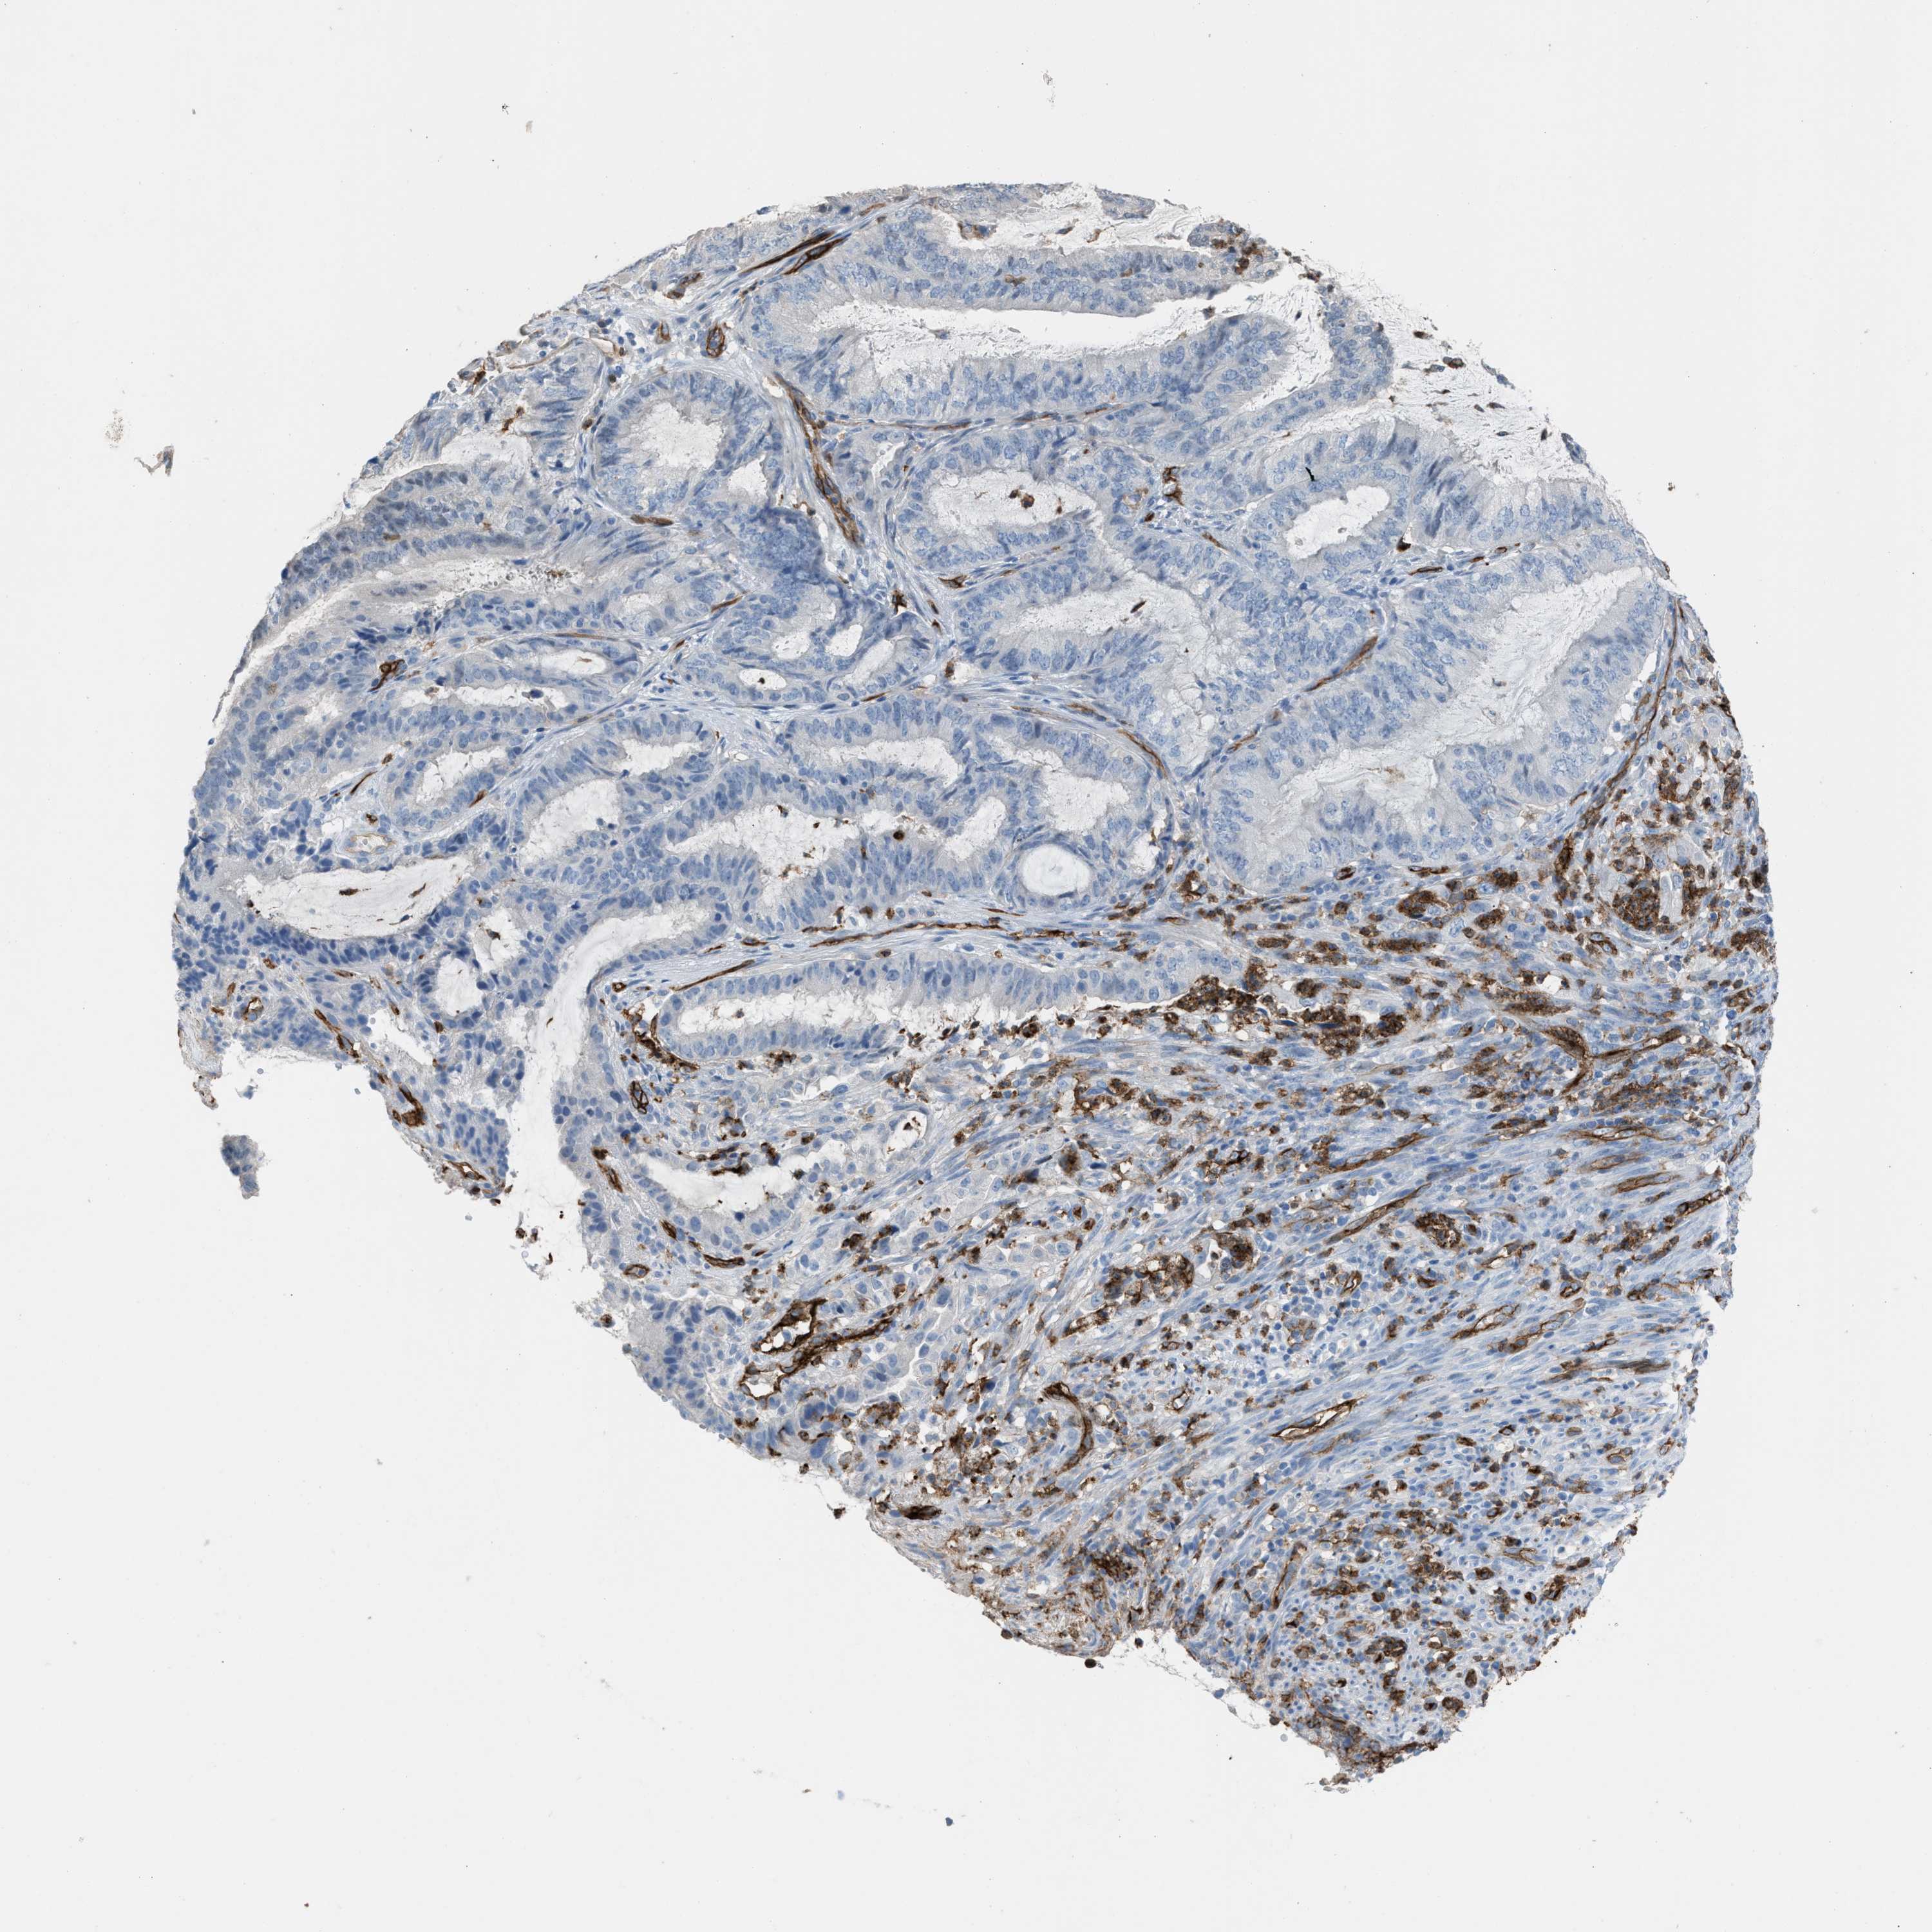

ENDOMETRIAL CANCER - Protein expressioni

A mouse-over function shows sample information and annotation data. Click on an image to view it in a full screen mode. Samples can be filtered based on level of antibody staining by selecting one or several of the following categories: high, medium, low and not detected. The assay and annotation is described here.

Note that samples used for immunohistochemistry by the Human Protein Atlas do not correspond to samples in the TCGA dataset.

Antibody stainingi

Antibody staining in the annotated cell types in the current human tissue is reported as not detected, low, medium, or high, based on conventional immunohistochemistry profiling in selected tissues. This score is based on the combination of the staining intensity and fraction of stained cells.

Each image is clickable and will lead to virtual microscopy that enables deeper exploration of all samples and also displays staining intensity scores, fraction scores and subcellular localization as well as patient and tissue information for each sample.

Antibody HPA017071

Antibody HPA021945

Antibody CAB002510

Staining

High

Medium

Low

Not detected

Intensity

Strong

Moderate

Weak

Negative

Quantity

>75%

75%-25%

<25%

None

Location

Nuclear

Cytoplasmic/membranous

Cytoplasmic/membranous,nuclear